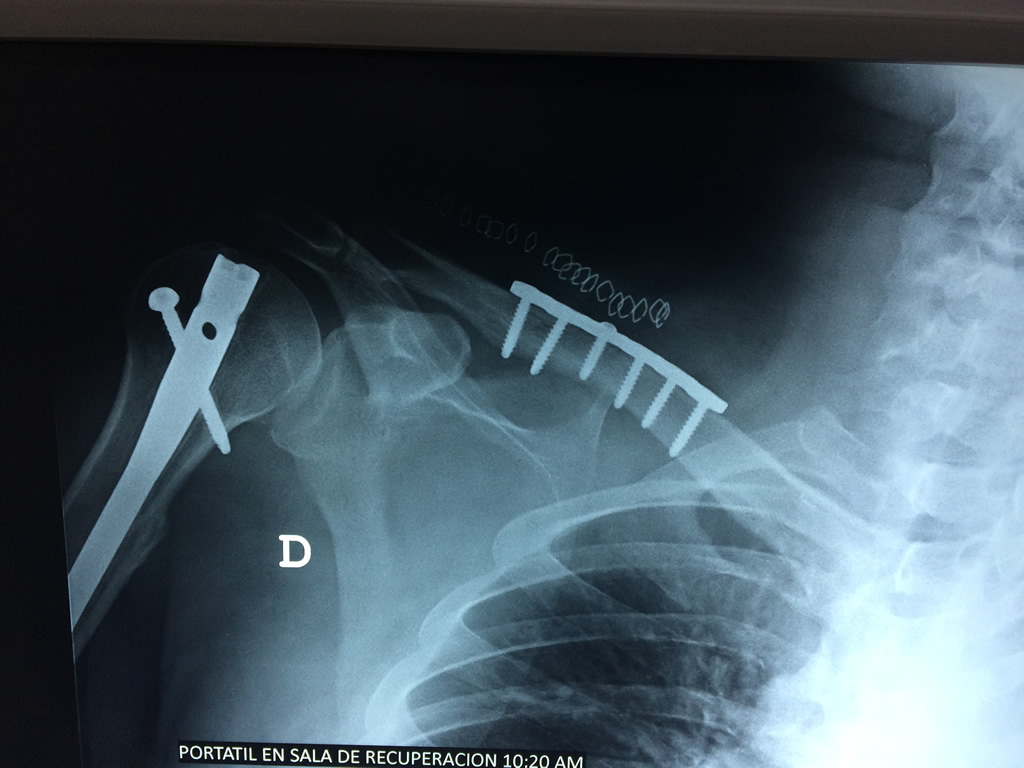

Húmero - Clavícula